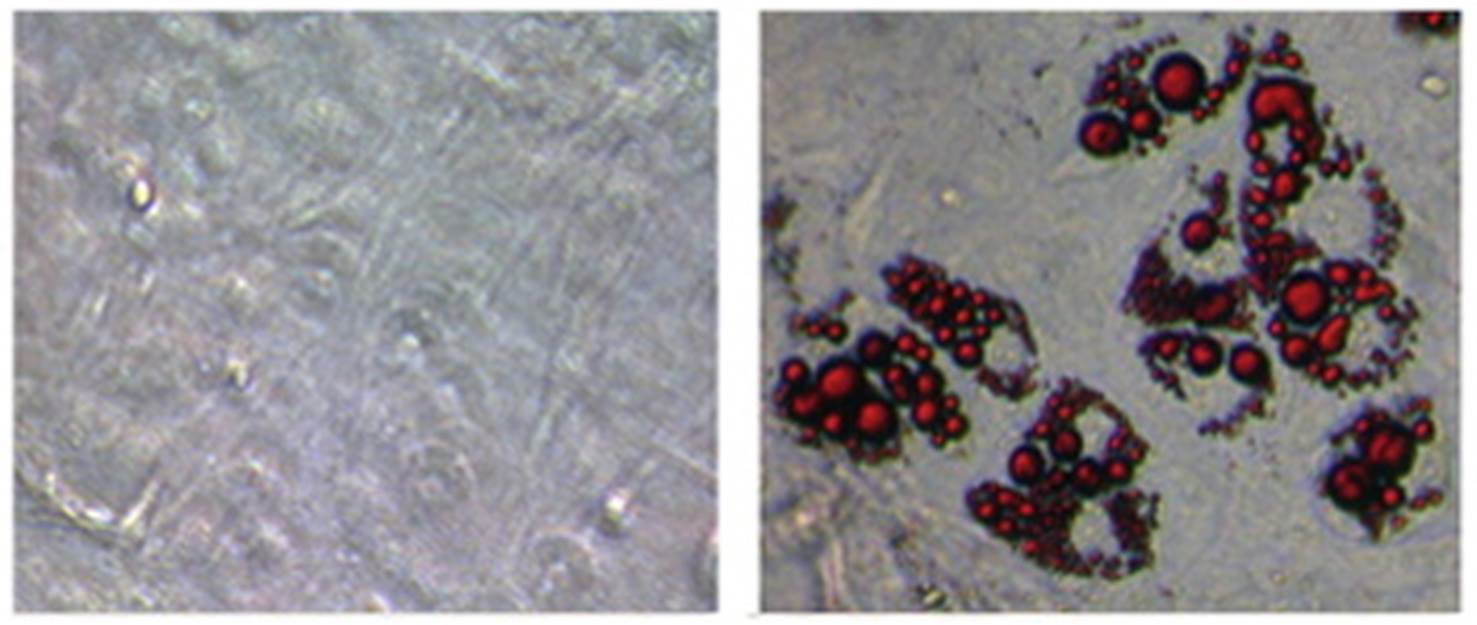

人體透過飲食,攝入的多餘能量會轉變成脂肪囤積在體內,從而導致肥胖。因此,阻斷脂肪吸收轉換和激活脂肪燃燒,都能有效地治療肥胖。香港大學理學院化學系研究助理教授王凱峰博士與柏克萊大學的研究團隊,發現人體內能激活白色脂肪轉化為燃燒脂肪 : 棕色脂肪的轉錄因子Zfp516蛋白。研究結果有助開發新藥物,透過直接刺激脂肪轉化燃燒而達到減肥效果,用以治療肥胖症,糖尿病和脂肪肝等新陳代謝疾病,有別於傳統藥物以壓抑食慾,阻斷脂肪在腸道吸收轉換,或是加快新陳代謝以達到減肥效果。

王博士與柏克萊大學的研究團隊的發現,揭開了人體形成棕色脂肪機制的面紗。在老鼠的實驗顯示,正常小鼠在攝氏4度的寒冷環境中待4小時,體溫約下跌3至4度,經基因改造使體內白色脂肪Zfp516蛋白含量高於正常的小鼠,體溫只微降1度,顯示牠們比一般小鼠有較強的耐寒能力。在另一實驗,基因小鼠與正常小鼠在常溫下被餵食相等的高脂餐單一個月後,前者體重增長比後者少30%,說明前者脂肪燃燒釋放了更多熱量。此外,基因小鼠的胰島素和葡萄糖的耐受性也有明顯改進。

近年來,激活棕色脂肪組織形成及讓其發揮功能,被視為是具前景的抗肥胖策略研究。由於棕色脂肪不僅能釋放熱量,還能影響代謝,因此在治療肥胖症,糖尿病和脂肪肝等新陳代謝疾病具有重要意義。研究結果有助新藥物的開發,透過增加人體轉錄因子蛋白,令白色脂肪在無須寒冷天氣的刺激下,也能自動轉化為棕色脂肪燃燒,無須運動配合,也能達到減肥的效果。 王博士說:「一般在低溫4度的寒冷環境刺激下,白色脂肪轉化為棕色脂肪燃燒保溫,一天大約消耗約600卡路里,相等於接近兩小時跑步所消耗的卡路里。日後透過增加Zfp516蛋白含量而將白色脂肪棕色化,在室溫下,也能達到同樣的消耗脂肪效果。」